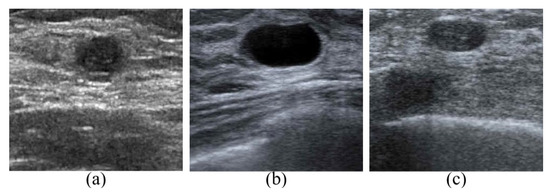

4.1. Image Preprocessing